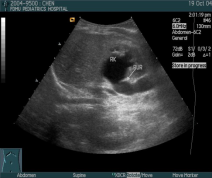

(三)影像学检查

1. B超检查

▪ USG – All f UTI patient, especially < 5 years